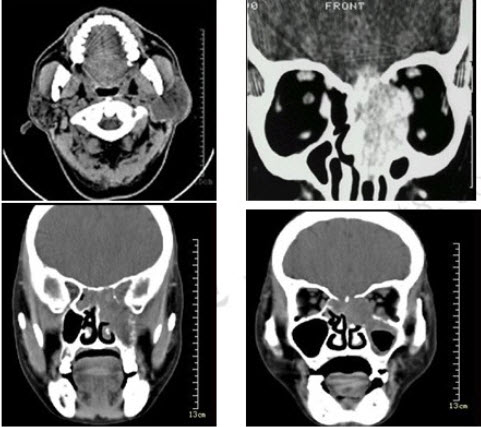

男性50岁,涕中带血半年,体检发现右侧颈部多个硬结,CT扫描如图所示,请选择正确的描述和结论()

A:右侧筛窦内见软组织块影,边缘不规则

B:软组织影累及对侧筛窦、右侧上颌窦

C:右侧眶内壁、上颌窦壁及颅底骨质破坏

D:考虑为右侧筛窦黏液性囊肿

E:考虑为右侧筛窦癌